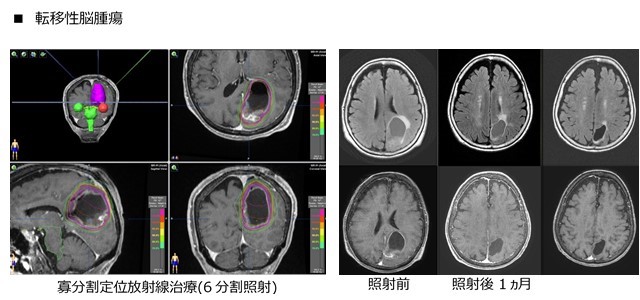

当院では、原則的に病変の最大径が25mm以下の場合は1回照射で、病変の最大径が25mm以上あるいは病変が小さくても照射体積内に

脳神経などの重要な構造物や重要な部位を含む場合は寡分割照射での治療を行っています。

- 転移性脳腫瘍